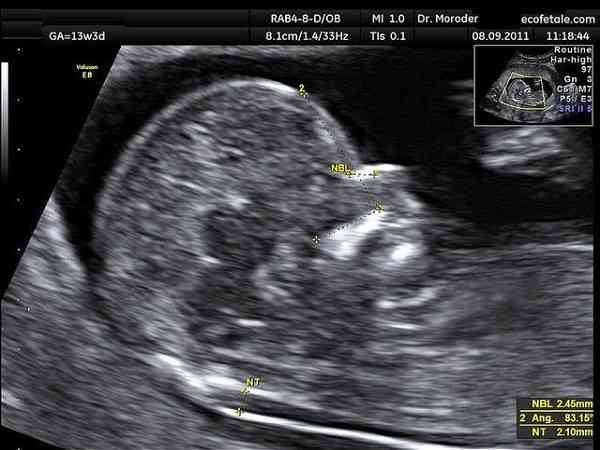

nt檢查結果值零點幾和一點幾的區別不大的,都是正常範圍。一般來說,如果nt值小於3mm,基本上都是沒有問題的。nt值資料的變化只是胎兒的新陳代謝以及後頸的透明層存在輕微的差異,但整體差距並不明顯。其實並沒有nt值零點幾和一點幾哪個好的說法,兩者都在正常範圍內,沒有什麼區別,資料的變化只是胎兒的新陳代謝,以及後頸的透明層存在輕微的差異,但整體差距並不明顯,不用太擔心,一般nt檢查正常情況是小於2.5毫米的,只要不超過這個範圍就是正常的現象。

NT檢查是用於評估胎兒是否有可能患有唐氏綜合徵的一種方法,是女性懷孕11-14周需進行的排畸檢查之一,由於每位女性檢查nt的時間不同,所以會出現相應的偏差,以下則是對nt檢查值的幾種情況分析: